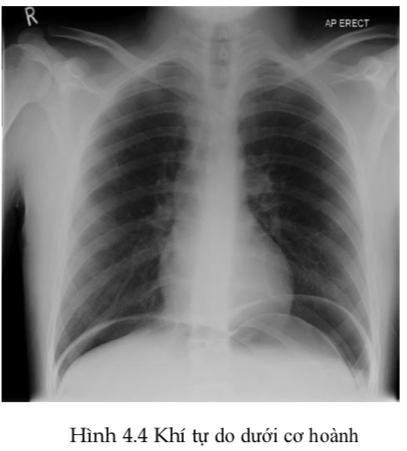

1. Có khí tự do trên x quang ngực đứng?

Thực hiện xquang ngực đứng ở tất cả bệnh nhân đau bụng trên cấp tính; sự hiện diện của khí tự do dưới cơ hoành cho biết thủng tạng rỗng. Bảo đảm đường truyền tĩnh mạch, phản ứng chéo máu, bồi phụ thể tích và chuyển phẫu thuật ngay lập tức.

Nếu xquang ngực không chứng minh có khí tự do hoặc tương đương nhưng nghi ngờ trên lâm sàng cao như đau bụng dữ dội khởi phát đột ngột với tăng cảm giác đau, đề kháng vùng thượng vị, cho chụp CT nhưng trước tiên cho làm amylase và ECG như mô tả ở bước 2 và 3.